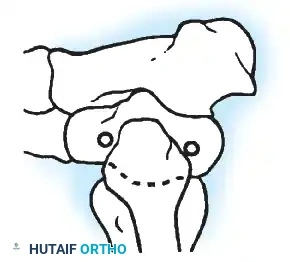

Knee Arthrodesis

While total knee arthroplasty (TKA) is the definitive treatment for knee osteoarthritis, knee arthrodesis remains a critical salvage procedure. The primary indications are a chronically infected TKA that has failed two-stage revision, massive extensor mechanism disruption, severe neuropathic arthropathy, and tumor resection.

Positioning and Technique

The optimal position for knee arthrodesis is 10 to 15 degrees of flexion and 5 to 7 degrees of valgus. This slight flexion assists in foot clearance during the swing phase of gait and makes sitting in confined spaces more manageable. A perfectly straight (0 degrees) knee is cosmetically awkward and functionally detrimental, causing a vaulting gait pattern.